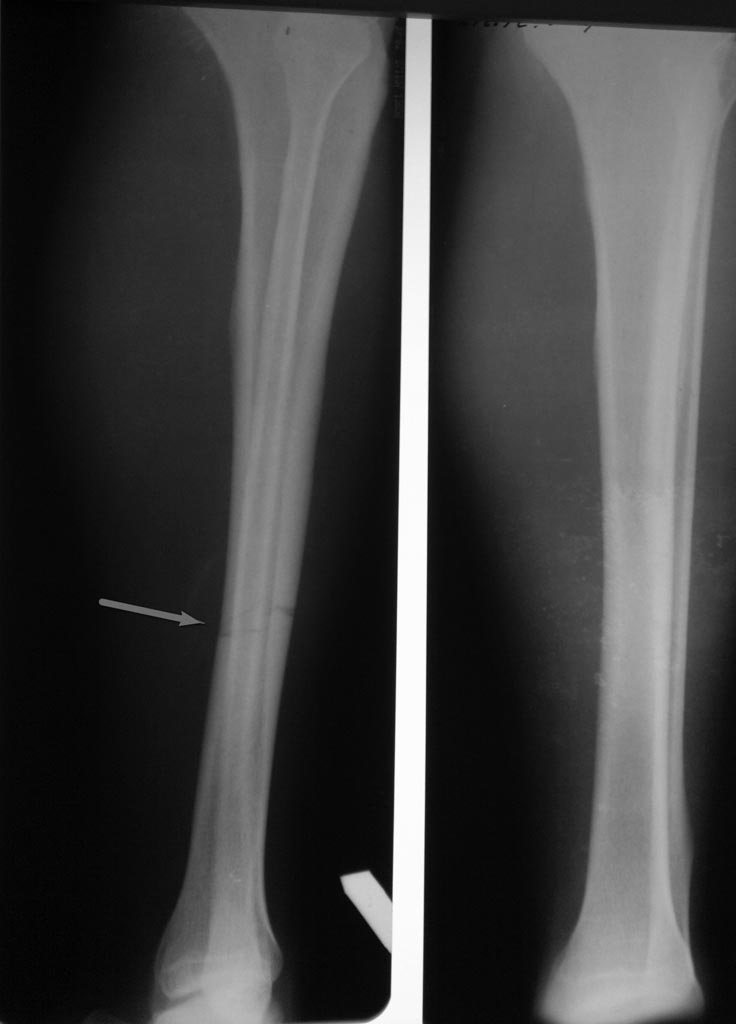

А где Вы увидели "незавершенный перелом"???

Вполне-таки нормальный поперечный перелом 4-2-A3 по классификации АО.

Сделайте прямую проекцию правильно, без ротации и сами в этом убедитесь.

Существует термин “неполный перелом” (incomplete fracture), когда линия перелома не пересекает поперечник кости. В основном встречается у детей, после стрессовых состоянии, а также после огнестрельных ран. Переломы у детей можно лечить консервативно, а у взрослых зависит от вовлечения диаметра кости. При вовлечении более 40% поперечника, во избежании перелома и смещения, нагрузочные кости лучше профилактически фиксировать.

В данном случае изолированный поперечный перелом большеберцовой без вовлечения малоберцовой. Проверка на деформацию и на крепитацию очень плохая идея!